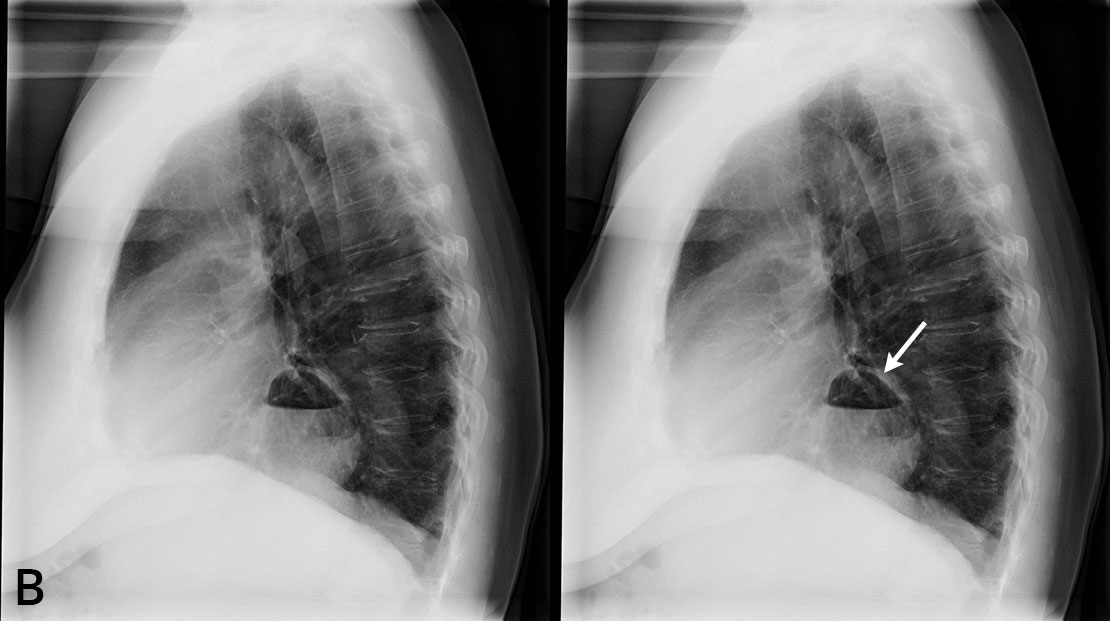

72-vuotias verenpainetautia ja munuaisten vajaatoimintaa sairastava nainen hakeutui tutkimuksiin heikentyneen rasituksensiedon ja hengenahdistuksen vuoksi. Potilaasta otettiin thoraxkuva ensisijaisena ajatuksena hengitystieinfektio tai sydämen vajaatoiminta.

A ja B. Sekä etu- että sivukuvassa ilmeni kookas palleatyrä, jonka sisällä oli ilmakupla. Sydän oli hieman normaalia kookkaampi, mutta keuhkoverekkyys normaalia. Hilukset ja ylämediastinum olivat siistit, eikä keuhkoparenkyymissa näkynyt poikkeavaa. Pleurasopet terävät. Muista tutkimuksista ilmeni, että huomattava osa ventrikkeliä oli hernioitunut mediastinumin puolelle. Vuoden päästä närästysvaiva hankaloitti elämää niin, että tehtiin ruokatorven varjoainekuvaus ja pohdittiin palleatyrän operatiivista hoitoa.